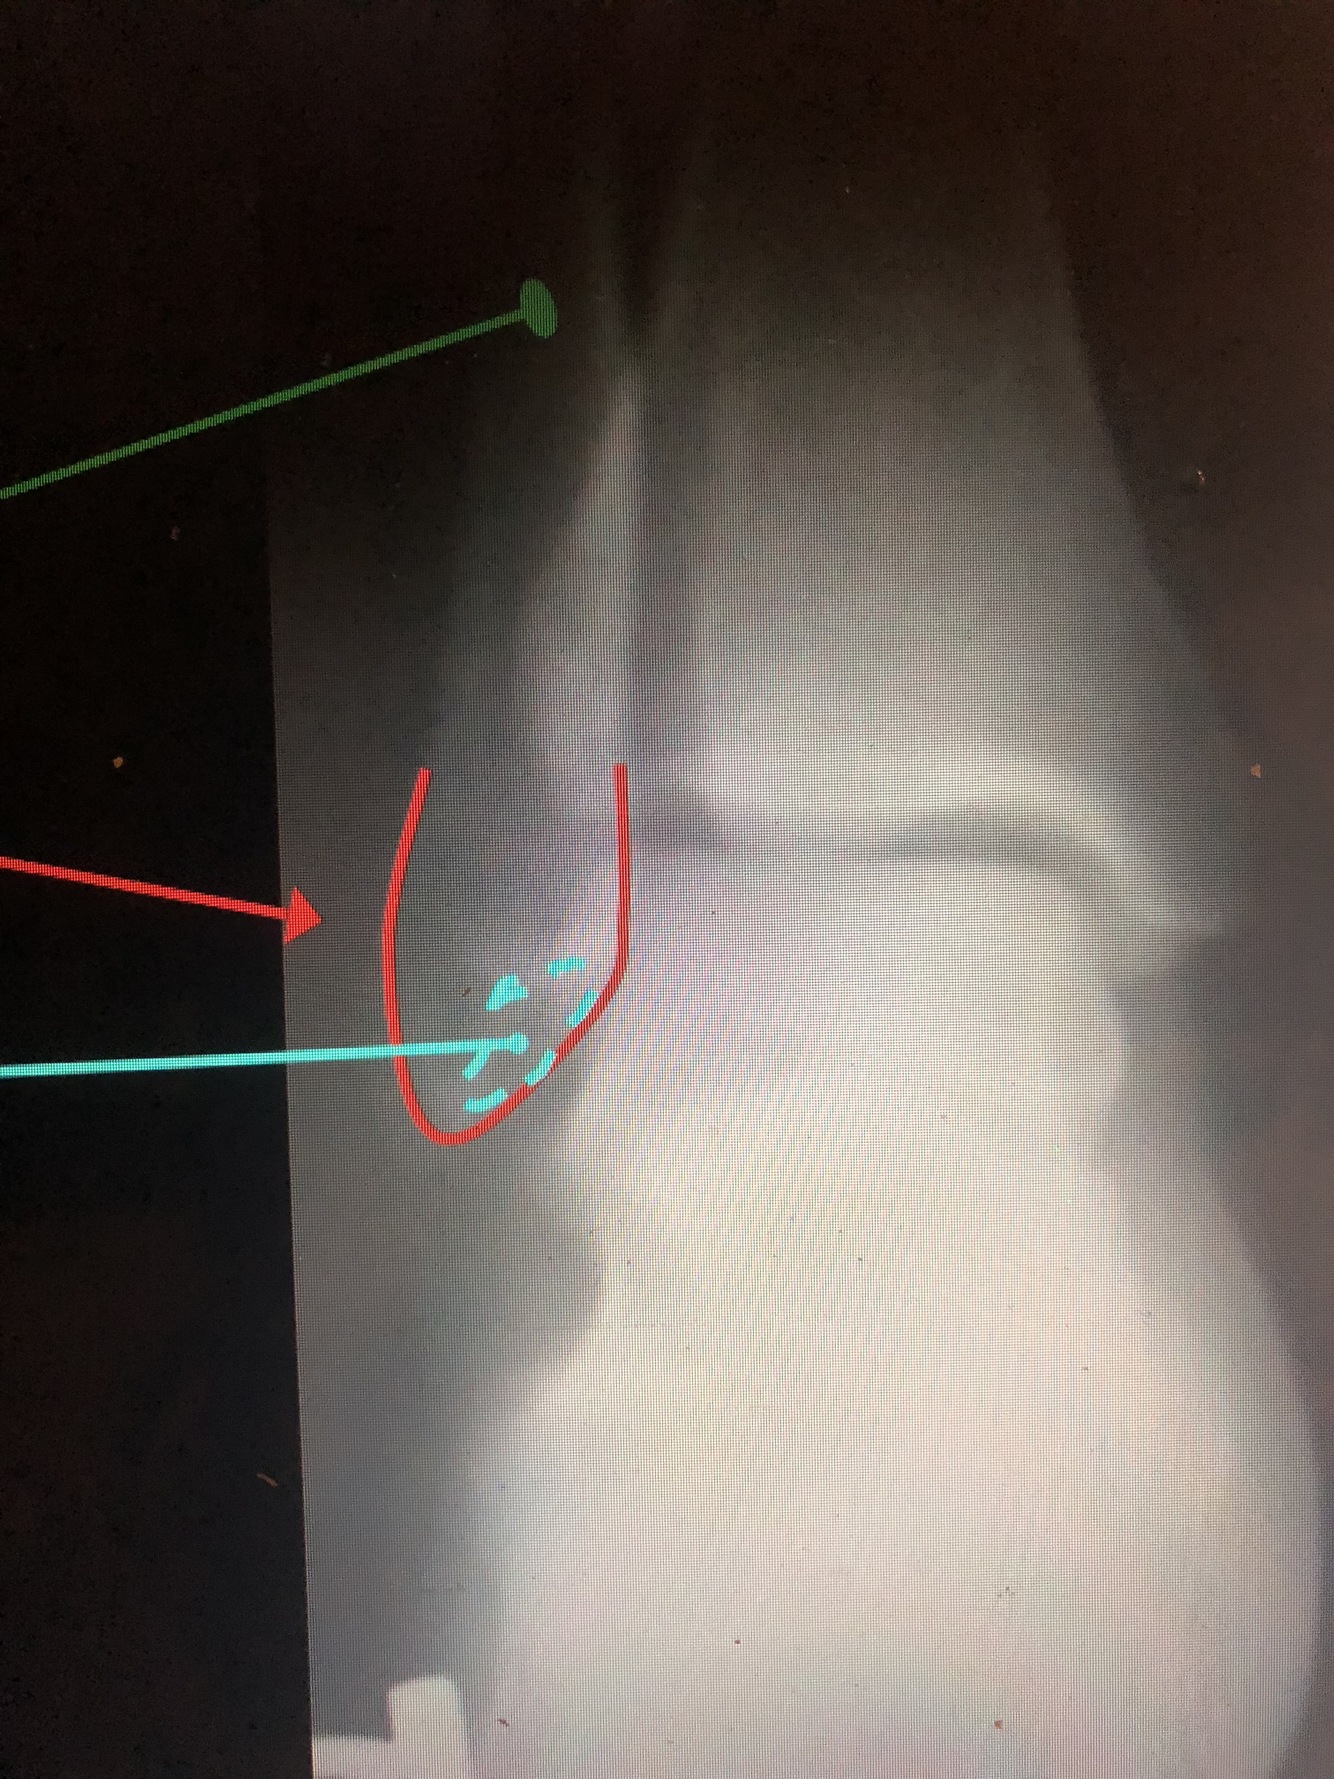

What is the yellow dotted line?

Fibular Notch

What is the dark blue line?

Plafond

What is the red line?

Posterior Malleolus

What is the light blue line?

Medial Malleolus

What is the blue line?

Lateral Malleolus